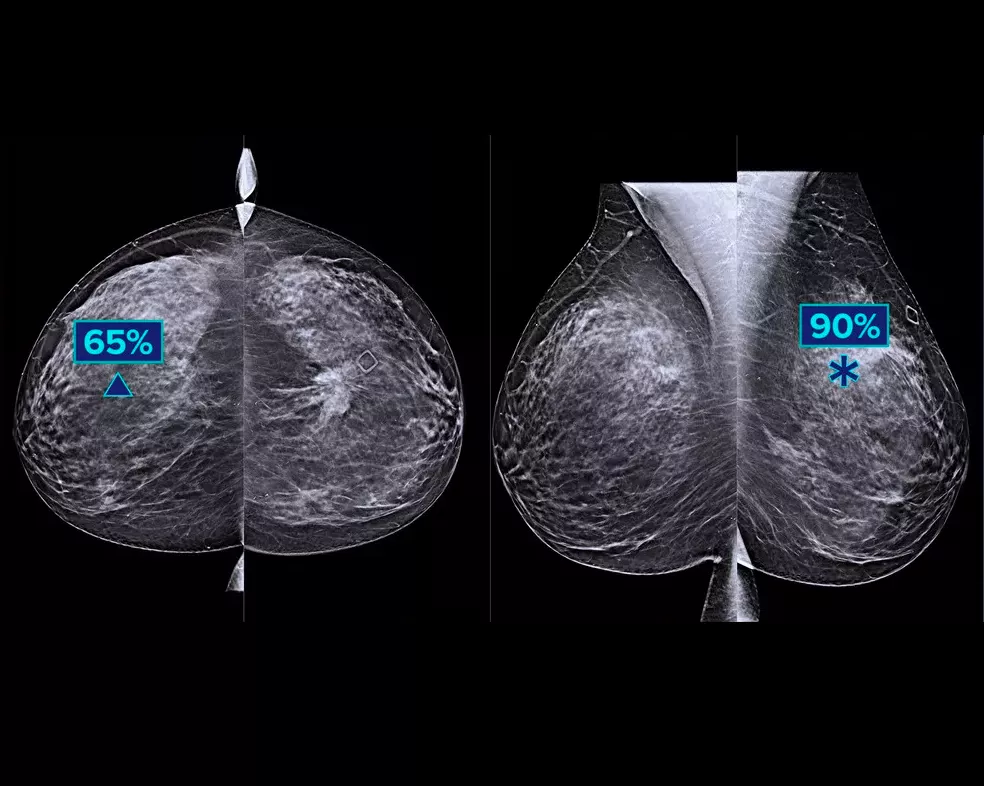

En un estudio se demuestra un aumento de +9 % en la sensibilidad del lector observada en los casos de cáncer.1.2 Puede utilizarse con imágenes de tomosíntesis de alta resolución y de resolución estándar y como superposición en SmartSlices de 3DQuorum e imágenes 2D sintetizadas.

El algoritmo busca los tres grupos principales de lesiones sospechosas: calcificaciones, masas, densidades y distorsiones, y las combinaciones de estas lesiones. Los resultados pueden variar dependiendo de la estación de trabajo de lectura.

Hologic ha realizado un estudio con múltiples casos y varios evaluadores (MRMC) para verificar el rendimiento cuando se utiliza el algoritmo de detección Genius AI.3